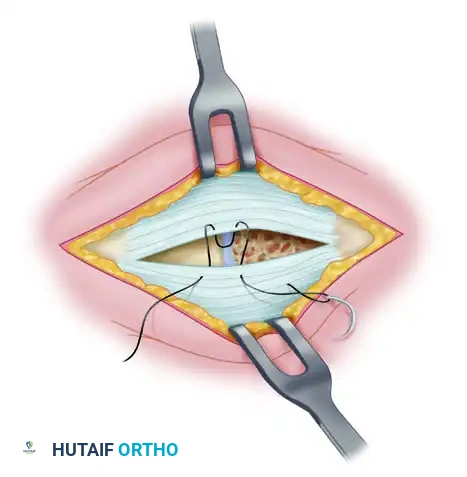

Medial Capsulorrhaphy and Closure

The final step is the medial capsulorrhaphy, which plicates the redundant medial capsule to hold the hallux in its newly corrected alignment.

- Hold the hallux in a congruently reduced position (approximately 0 to 5 degrees of valgus). Avoid over-correcting into varus.

- Excision of a redundant wedge of the medial capsule may be necessary.

- Imbricate the medial capsule, typically bringing the plantar flap over the dorsal flap, using strong, absorbable sutures (e.g., 2-0 Vicryl).

- Ensure the tension is sufficient to maintain the correction but not so tight as to restrict MTP joint plantarflexion and dorsiflexion.

- Deflate the tourniquet and achieve meticulous hemostasis.

- Close the skin incisions with non-absorbable monofilament sutures (e.g., 4-0 Nylon) using a horizontal mattress or simple interrupted technique.